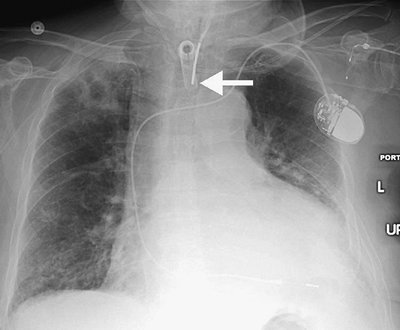

FIGURE 5-11. Pulmonary artery pseudoaneurysm as a complication of pulmonary artery catheter placement. A: AP recumbent chest radiograph in a 66-year-old woman with a history of chronic obstructive pulmonary disease and prior lung volume reduction surgery. The film was taken shortly after right heart catheterization, during which time a pulmonary artery catheter was placed into the right pulmonary artery to measure pulmonary capillary wedge pressure. The radiograph shows diffuse airspace disease in the right lung, consistent with acute pulmonary hemorrhage, which was new compared with a precatheterization radiograph. B: CT scan obtained after administration of intravenous contrast material, performed the same day as the chest radiograph in (A), shows an enhancing peripheral pulmonary artery pseudoaneurysm (arrows), with surrounding pulmonary hemorrhage (arrowheads). The pseudoaneurysm was embolized with coils by interventional radiologists, and the bleeding stopped.

Aortic dissection can occur during IABP insertion, which may result in death (16). Other potential complications include reduction of platelets, red blood cell destruction, peripheral emboli, balloon rupture with gas embolus, renal failure, and vascular insufficiency of the catheterized limb (17) (Table 5-3).